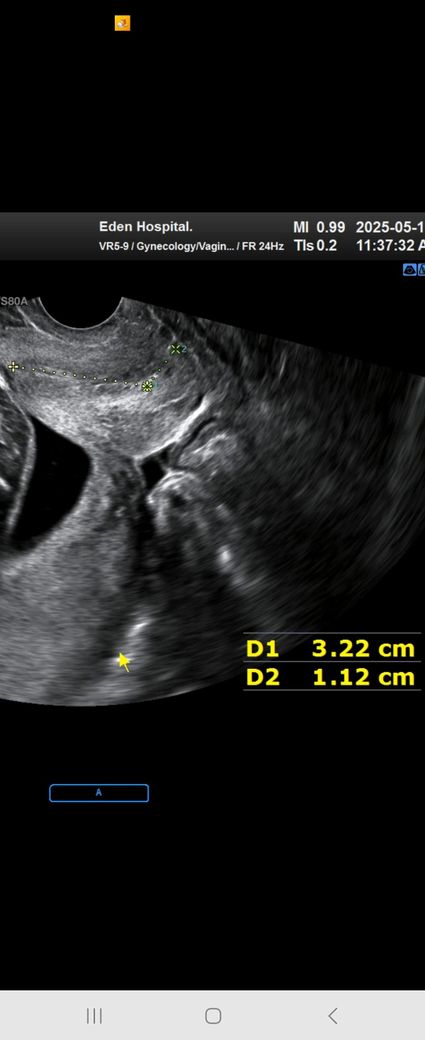

D1노란줄 3.22

녹색줄 d2 1.12 인데요 두번 나눈건데 합쳐진값이 경부길이인가요?

지난주 초반에 3.95 이고

배뭉침으로3일전3.85인 오늘 쟀는데 길이를 말씀 못해주셔서 궁금해서요ㅜ